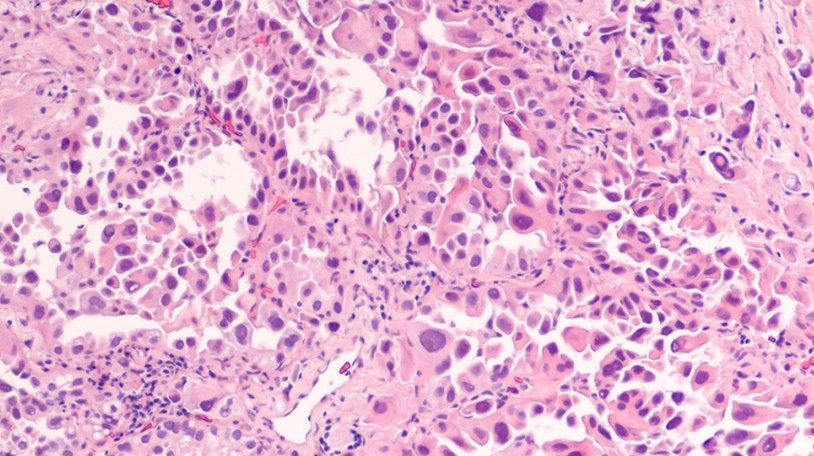

非小细胞肺癌(NSCLC)在肺癌中占据较大比例,其治疗的突破对于改善肺癌患者的整体预后至关重要。目前,针对 NSCLC 的治疗正朝着精准化、多样化的方向发展,新的治疗药物和方案不断涌现,为患者提供了更多的选择。

小细胞肺癌(SCLC)具有恶性程度高、进展快的特点,传统治疗手段有限。近年来,免疫治疗和新药的研发为 SCLC 的治疗带来了新的突破,显著改善了患者的预后。